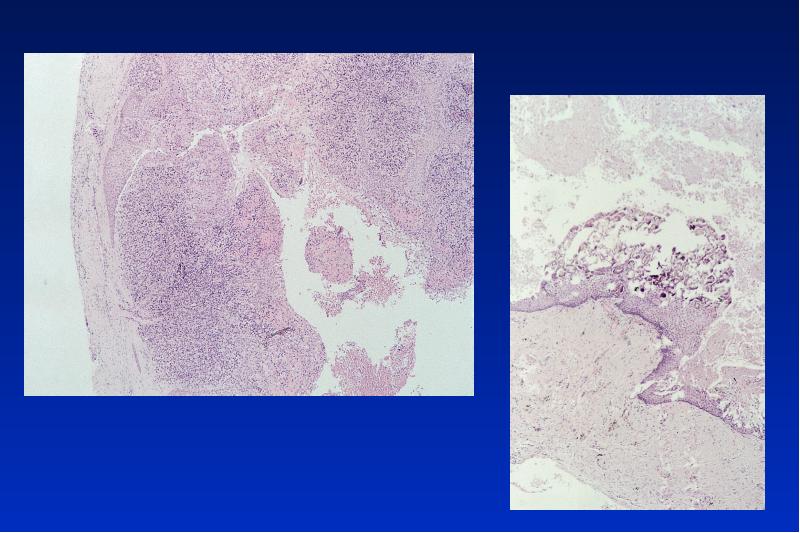

- 21. Odontogene Keratozyste Lok: UK Alter: 20 - 30, 50 - 60

- 23. Gorlin-Goltz Syndrom autosomal dominanter Erbgang Symptome: multiple